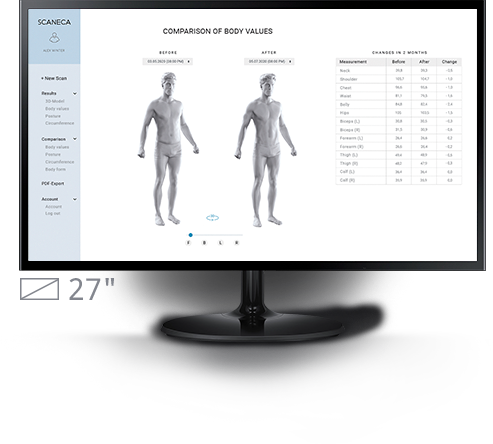

Met SCANECA herkent u houdingsproblemen in één oogopslag. De verdeling

van de belasting over de voeten en de belangrijkste afstanden en hoeken worden automatisch bepaald.

Met de handige visualisatie kan iedereen de analyse van een trainer of therapeut volgen en de therapie succesvoller uitvoeren.